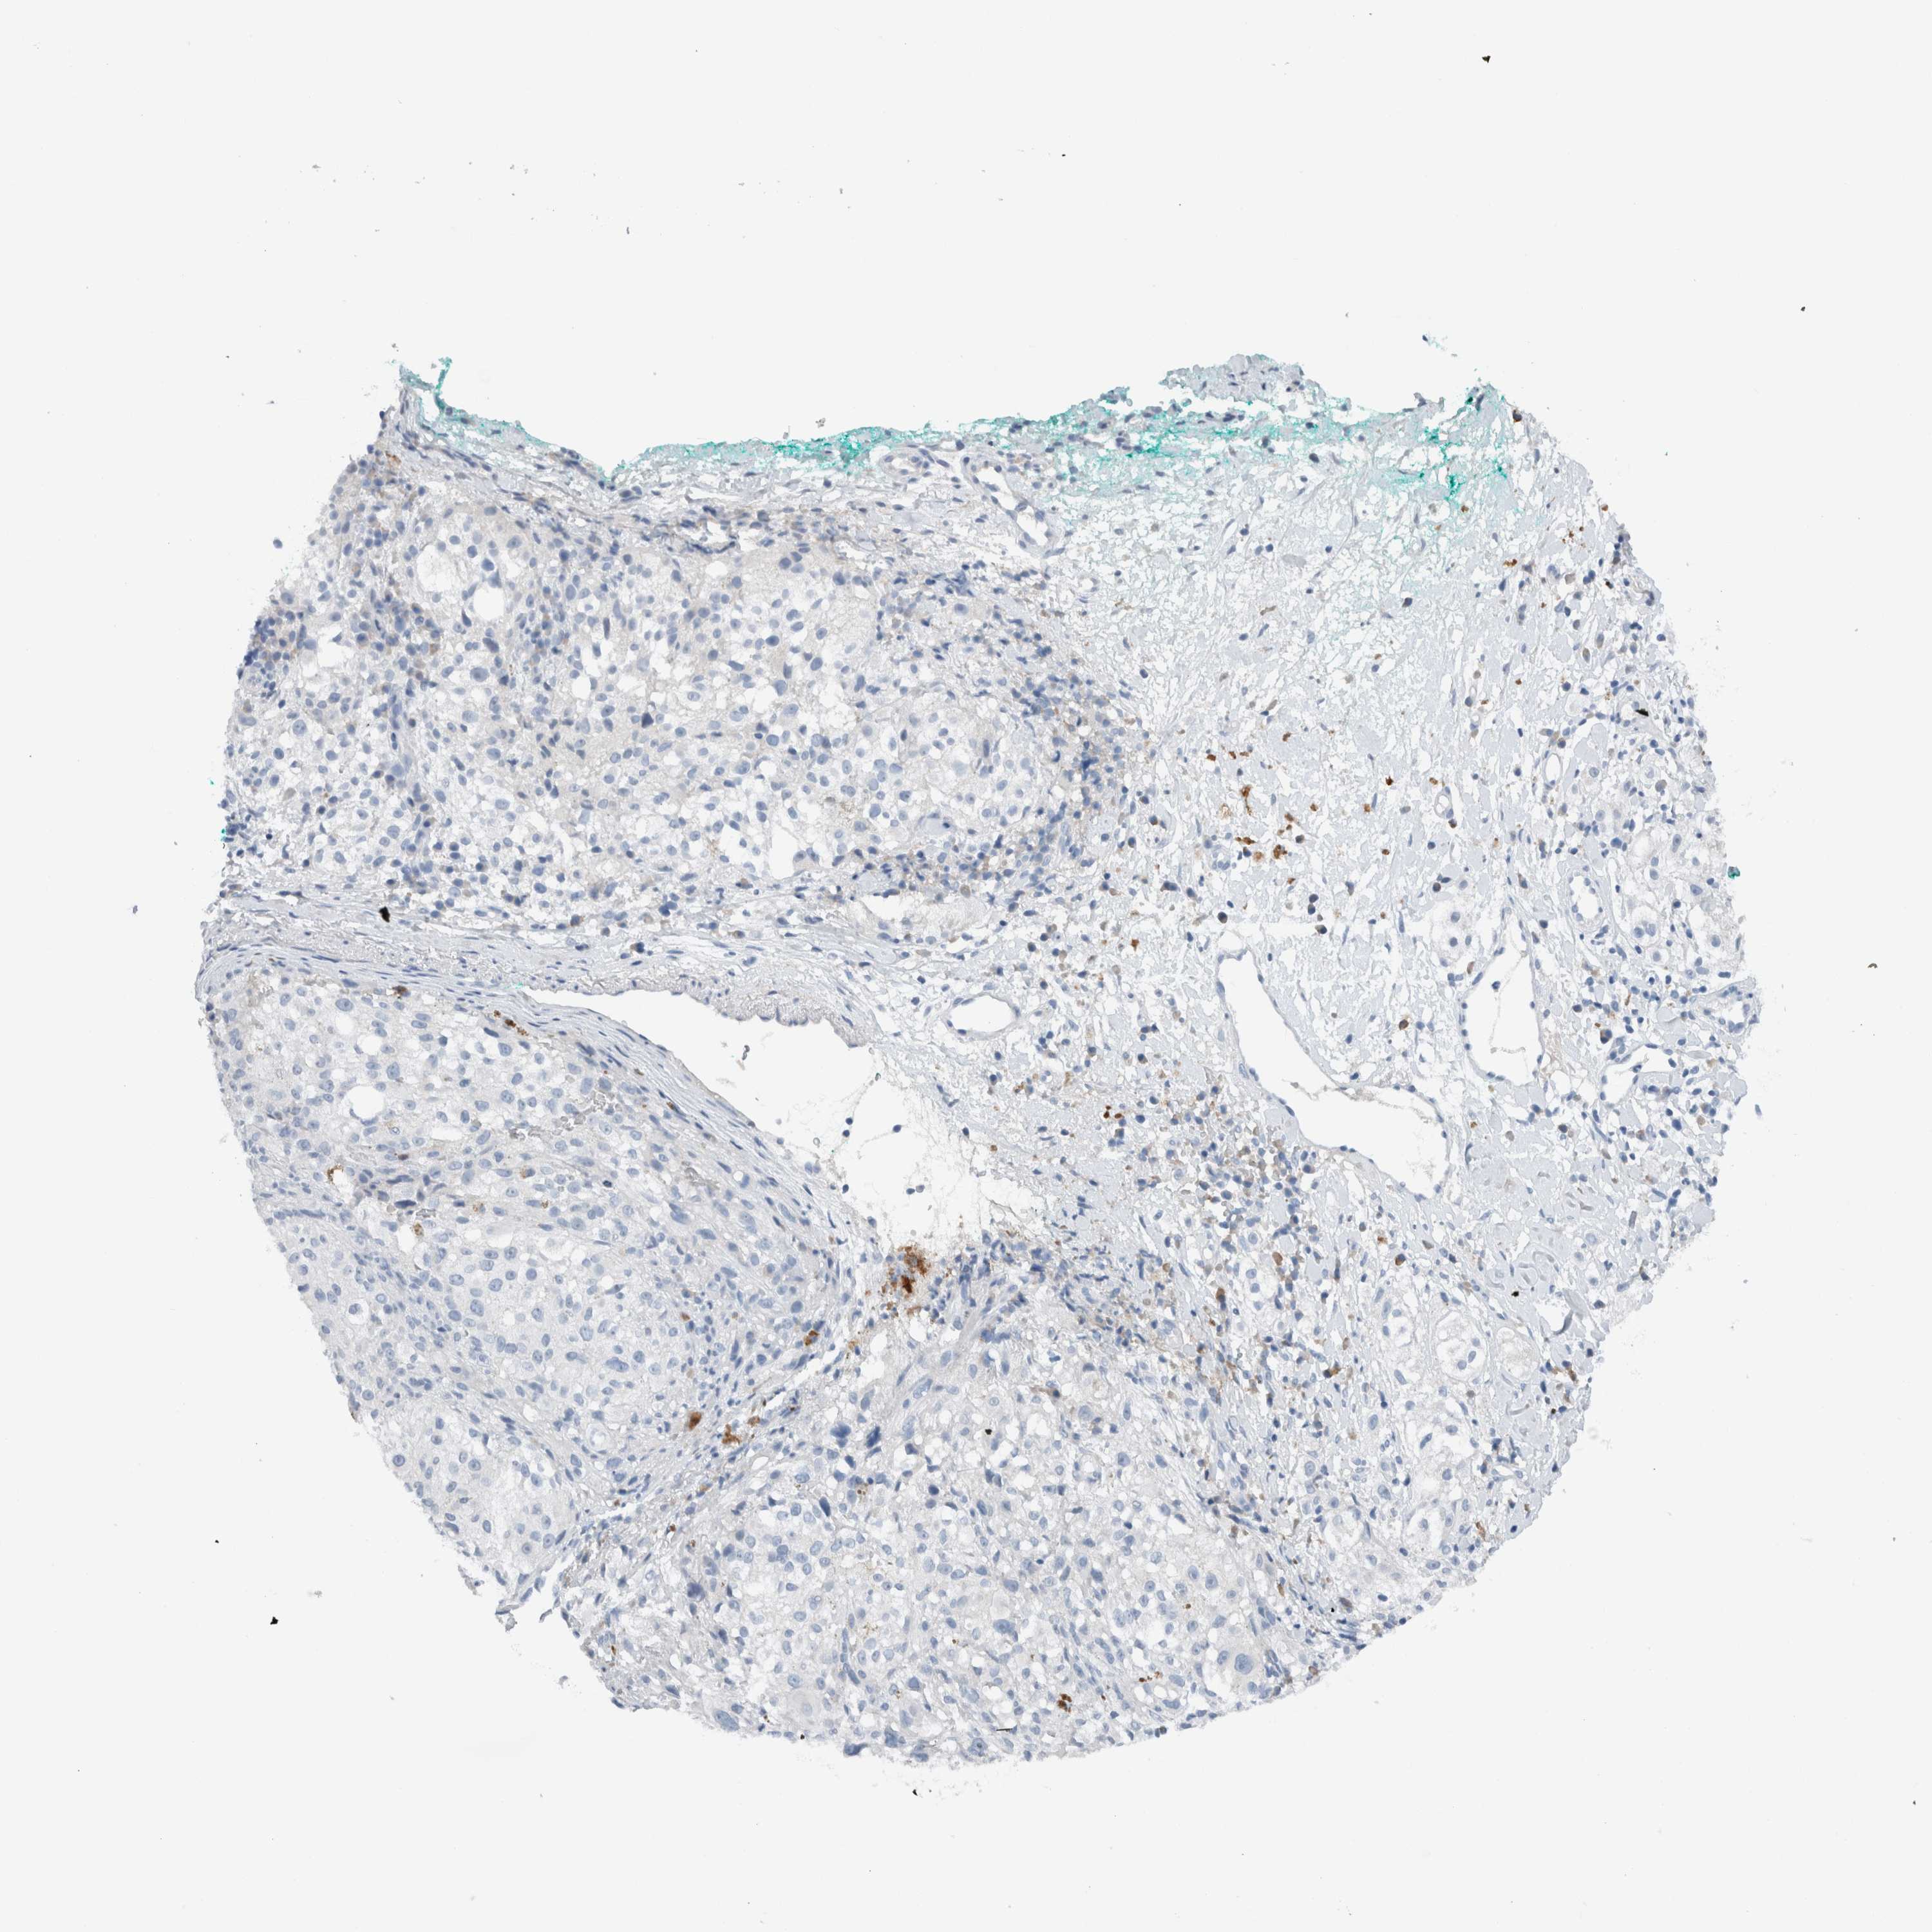

MELANOMA - Protein expressioni

A mouse-over function shows sample information and annotation data. Click on an image to view it in a full screen mode. Samples can be filtered based on level of antibody staining by selecting one or several of the following categories: high, medium, low and not detected. The assay and annotation is described here.

Note that samples used for immunohistochemistry by the Human Protein Atlas do not correspond to samples in the TCGA dataset.

Antibody stainingi

Antibody staining in the annotated cell types in the current human tissue is reported as not detected, low, medium, or high, based on conventional immunohistochemistry profiling in selected tissues. This score is based on the combination of the staining intensity and fraction of stained cells.

Each image is clickable and will lead to virtual microscopy that enables deeper exploration of all samples and also displays staining intensity scores, fraction scores and subcellular localization as well as patient and tissue information for each sample.

Antibody HPA023544

Staining

High

Medium

Low

Not detected

Intensity

Strong

Moderate

Weak

Negative

Quantity

>75%

75%-25%

<25%

None

Location

Nuclear

Cytoplasmic/membranous

Cytoplasmic/membranous,nuclear

Malignant melanoma, NOS

Malignant melanoma, Metastatic site